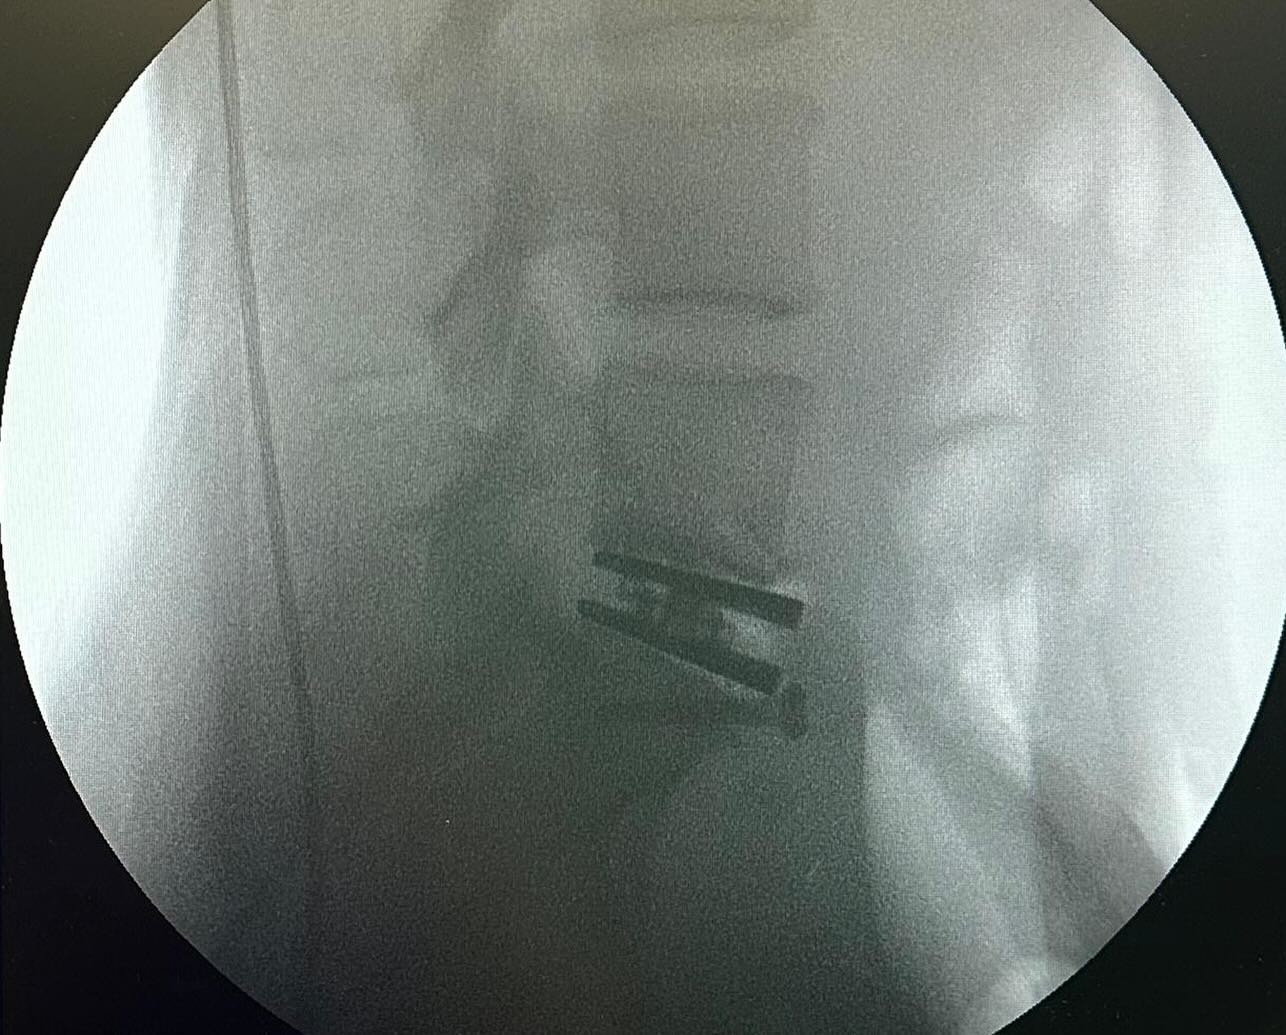

一向熱愛運動,有「肯雅徐」封號嘅徐濠縈,不時喺社交平台分享上山下海嘅運動相,但係近日佢就分享咗兩張腰椎嘅X光相,另外仲有喺手術室嘅環境相同寫有「加油!媽媽」等相關相片。

阿徐亦喺帖文以英文寫上自己情況,佢透露自己由於腰椎間盤突出問題,多年嚟一直患有背痛。喺2022年時,佢接受咗手術切除剩餘嘅椎間盤,但係下背部疼痛仍然存在。

作為一個非常活躍嘅人,佢話自己過去嘅兩年特別具有挑戰性,因為不得不停止重量訓練,喺野外滑雪,由於要攜帶沉重裝備,佢經歷過背部疼痛。呢種情況影響咗佢日常生活,每當打噴嚏時都會感到劇烈疼痛。結果喺醫生建議下,佢決定進行椎間盤置換手術。